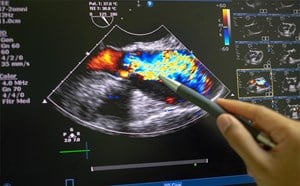

We present the case of a 15-year-old female patient with no known past medical history who presented to a transient medical clinic in the remote territory of La Moskitia, Honduras with a three-month history of poor appetite, nausea, vomiting, and worsening epigastric pain. She was initially diagnosed as gastritis at an external clinic. However, a point-of-care ultrasound examination was performed, and she was diagnosed with a small bowel obstruction (SBO) (Figure 1). During her visit, she had an episode of emesis, which demonstrated a large worm consistent with an Ascaris lumbricoides (Figure 2). The etiology of the SBO was suspected to be secondary to physical obstruction from the Ascariasis obstruction.

Figure 1. Portable ultrasound that was used to diagnose a small bowel obstruction.

Ultrasonography has been shown to be a useful adjunct in the evaluation of patients with suspected SBO as it can be performed rapidly and with high accuracy, even when performed under minimal training.6,7 The diagnosis is made based upon a small intestinal diameter of greater than 2.5 cm with abnormal peristalsis.6 A recent systematic review and meta-analysis found that ultrasound was 92.4% sensitive and 96.6% specific with a positive likelihood ratio of 27.5 and a negative likelihood ratio of 0.08.8 Therefore, ultrasound can be a valuable adjunct for making the diagnosis and is particularly valuable in areas where access to advanced imaging is limited. In this case, ultrasound was able to make the diagnosis and lead to transfer to an advanced healthcare facility, which may not have otherwise been possible.